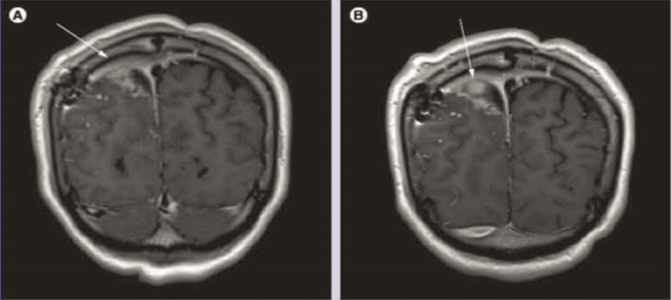

Gadobutrol (A & B) contrast - enhanced spin-echo T-weighted coronal brain images in a patient with brain tumor and postsurgical changes. shows dural enhancement ( A, arrow) at the right and left of the tumor with the presence of nodular area of enhancement ( B, arrow) (A & B) show a better degree of enhancement and internal morphology.